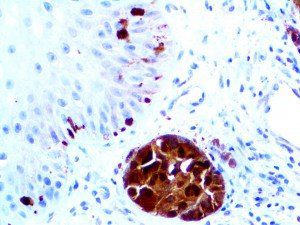

It is the ICU physician who is most likely to witness one of the deadliest manifestations of the abnormal immunological response, the cytokine storm syndrome (CSS). This response is also referred to by some as the cytokine release syndrome (CRS). CSS is characterized by continuous activation and expansion of macrophage and lymphocyte populations, which secrete large amounts of cytokines, causing the cytokine storm. This massive cytokine release is akin to hemophagocytic lymphohistiocytosis (HLH) disease, a syndrome characterized by initial unchecked and persistent activation of cytotoxic T lymphocytes and NK cells.

Clinical and laboratory manifestations of HLH include fever, enlarged liver and/or spleen, neurologic dysfunction, coagulopathy, liver dysfunction, cytopenias (i.e., low levels of erythrocytes, leukocytes, and/or platelets), hypertriglyceridemia, hyperferritinemia, hemophagocytosis, and eventually diminished NK cell activity as the immune system becomes progressively paralyzed. HLH can be familial (primary HLH) or secondary to another disease process (sHLH), such as rheumatic disease, in which it is referred to as macrophage activation syndrome (MAS, characterized by elevated ferritin).